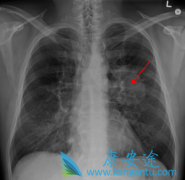

肺癌的早筛麻烦点在于,目前还没有有针对性的 肺癌 生化指标,同时体检胸片对早期肺癌的发现效果并不特别理想。这就代表在早期更多的需要凭借各级医生对临床 肺癌的症状 的判断来进行筛查,不仅是专科医生,负责全科诊疗的社区医生和家庭医生也应加以重 ...